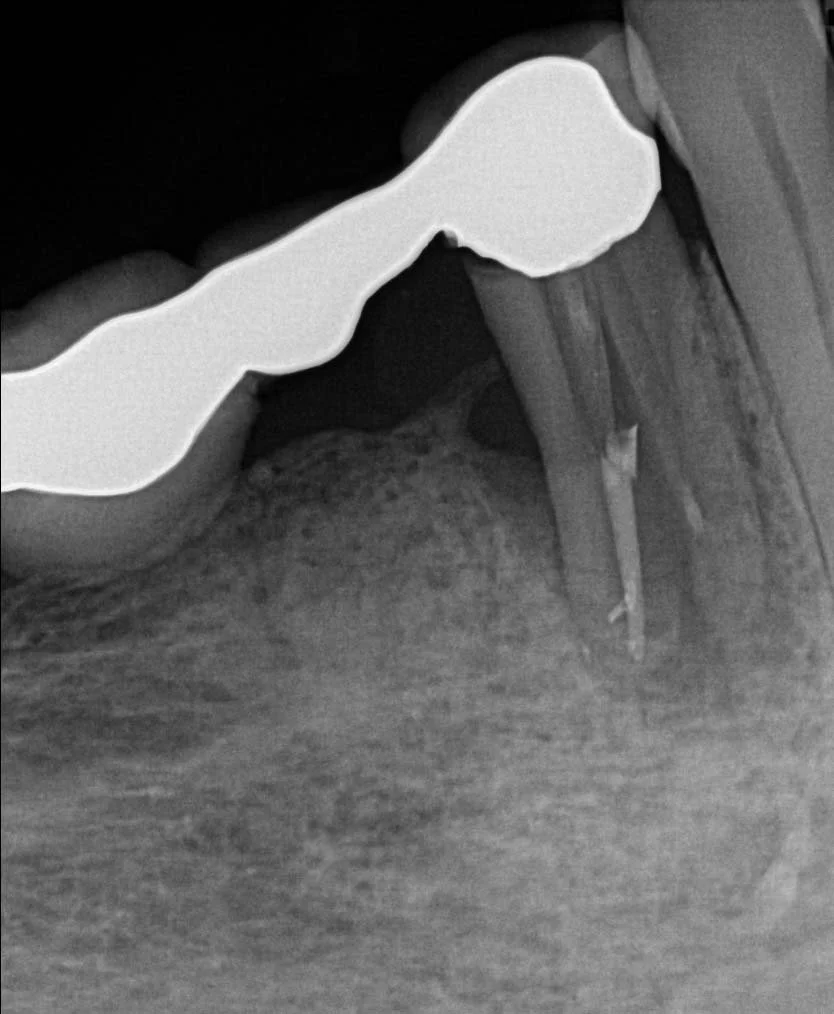

Once healing and adequate bone volume above the mandibular canal had been confirmed, two Bioconcept 3.3mm x 10mm tissue level implants were placed in sites 44 and 46. Several careful progressive intraoperative periapical radiographs were taken to confirm vertical position relative to the mandibular canal. Both implants were then placed with a primary stability of over 30 Ncm as a one stage surgical procedure, and 2mm healing abutments were then secured.

Following three months healing time, osseo-integration was then confirmed with the usual methods, combined with ISQ measurements (Ostell), to confirm readings of over 65 for adequate stability to allow for restoration.

Open tray screw retained impression copings were then attached and confirmed with radiographs, and a three-unit veneered zirconia bridge was constructed using Variobase lab cemented abutments to provide an all-in-one screw-retained restoration.